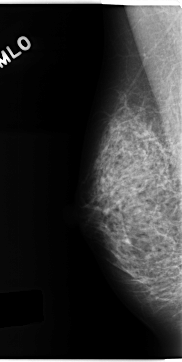

C_0153_1.RIGHT_MLO

RIGHT_MLO LINES 4704 PIXELS_PER_LINE 2360 BITS_PER_PIXEL 12 RESOLUTION 50 NON_OVERLAY